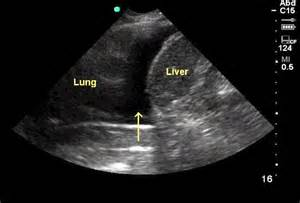

USM – plevral mayeni göstərir.

Plevrada mayeni rentgen göstərə bilər. Qabırğa-diafraqma cibinin düzləşməsi, plevrada homogen kölgəlik, Damuaze xətti mayenin rentgenoloji əlamətləridir. Qabırğa-diafraqma xəttinin düzləşməsi plevrada ən azı 250 ml mayenin olduğunu göstərir. Lakin, mayeni görmək üçün ən həssas müayinə USM-dir.